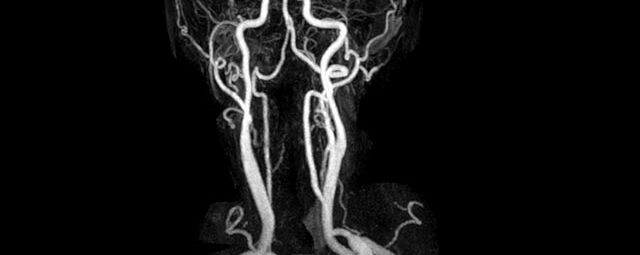

MR-Angiografie (MRA)

• MR-Angiografie ohne Kontrastmittel

• Time of Flight (TOF)-Angiographie

Je nach Fragestellung und Körperregion Gefäßdarstellung ohne Kontrastmittel bei Kontrastmittelunverträglichkeit oder terminaler Niereninsuffizienz möglich.

• MR-Angiographie mit Kontrastmittel

• Erfassung arterieller und venöser Gefäße/Bypässe aller Körperregionen mit 3D-Rekonstruktion